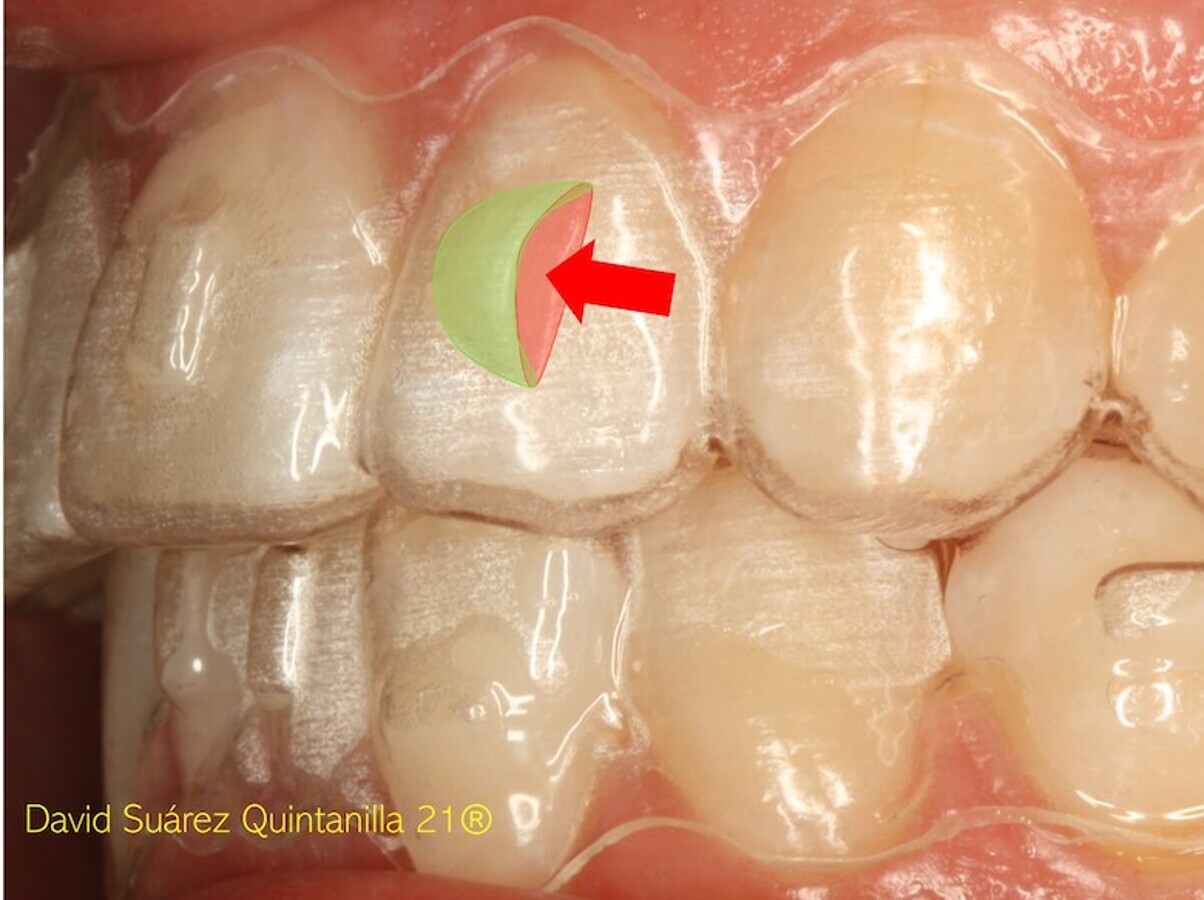

La elasticidad de los plásticos actuales ha mejorado mucho la eficiencia biomecánica de los alineadores pero para su mayor eficacia biomecánica necesitamos añadir ataches que incrementen la superficie de contacto con el alineador en la dirección deseada. Sin ataches no es sencillo rotar dientes de superficie esférica (figura 4).

Figura 4. Aunque la elasticidad de los plásticos actuales ha mejorado mucho la eficiencia biomecánica de los alineadores, es necesario añadir ataches para rotar dientes de superficie esférica.

Caso tratado con alineadores, ataches activos de rotación de cuarto de esfera en caninos y orthostripping de 0,75 mm/diente en la parte anterior de la arcada superior (figura 30).

Figura 30. Caso clínico tratado con alineadores, ataches activos de rotación de cuarto de esfera en caninos y orthostripping de 0,75 mm/diente en la parte anterior de la arcada superior.